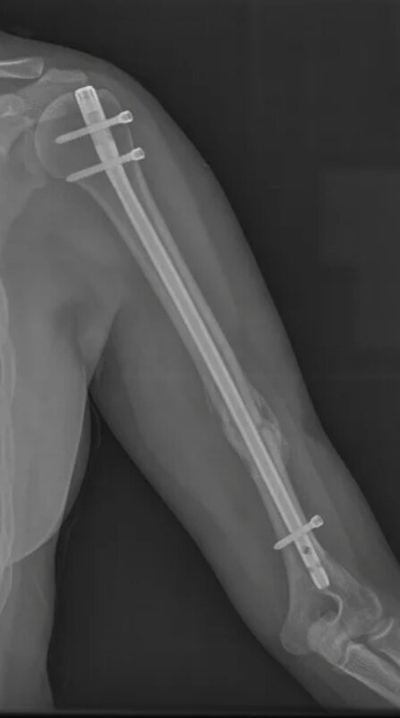

Продолжаем пропитываться народной мудростью и залихватски петь о том, что происходит вокруг. А вокруг меня сейчас происходит больничный и восстановление после остеосинтеза плеча (это когда разломанные кости собирают в монолит, обогащая организм железкой и винтами). Так что как бы ни хотелось, а байки из секс-шопа теперь с уклоном в область травматологии. Но! Наш народ такой ерундой не победить и на днях была поднята тема предстоящей человеку операции, что натолкнуло на написание этого поста Перед операцией и после неё мне отсыпали советов от товарищей, которые частично или полностью смонтированы на пластинах, винтах, скобах, штырях и прочем металле. От насоветованного и перспектив у меня теперь седина во всех местах, но избежать многих неприятностей они мне помогли. Плюс мои наблюдения и полученный лично опыт.